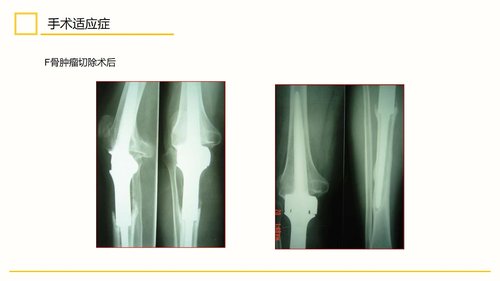

该手术主要适用于膝关节单间室退行性骨关节炎、类风湿性关节炎、强直性脊柱炎、创伤性关节炎、结核或肿瘤术后强直等多种疾病导致的局限性严重疼痛和功能障碍,尤其对于伴有内翻、外翻或屈曲挛缩等畸形的病例具有明确指征。其禁忌症主要包括关节周围或全身活动性感染,以及可能导致全膝置换术后关节不稳的各类疾病。